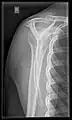

X-ray

Projectional radiography views of the shoulder include:

- AP-projection 40° posterior oblique after Grashey

The body has to be rotated about 30 to 45 degrees towards the shoulder to be imaged, and the standing or sitting patient lets the arm hang. This method reveals the joint gap and the vertical alignment towards the socket.[24]

- Transaxillary projection

The arm should be abducted 80 to 100 degrees. This method reveals:[24]

- The horizontal alignment of the humerus head in respect to the socket and the lateral clavicle in respect to the acromion

- Lesions of the anterior and posterior socket border, or of the tuberculum minus

- The eventual non-closure of the acromial apophysis

- The coraco-humeral interval

CR. shoulay film.

Transaxillary conventional radiography